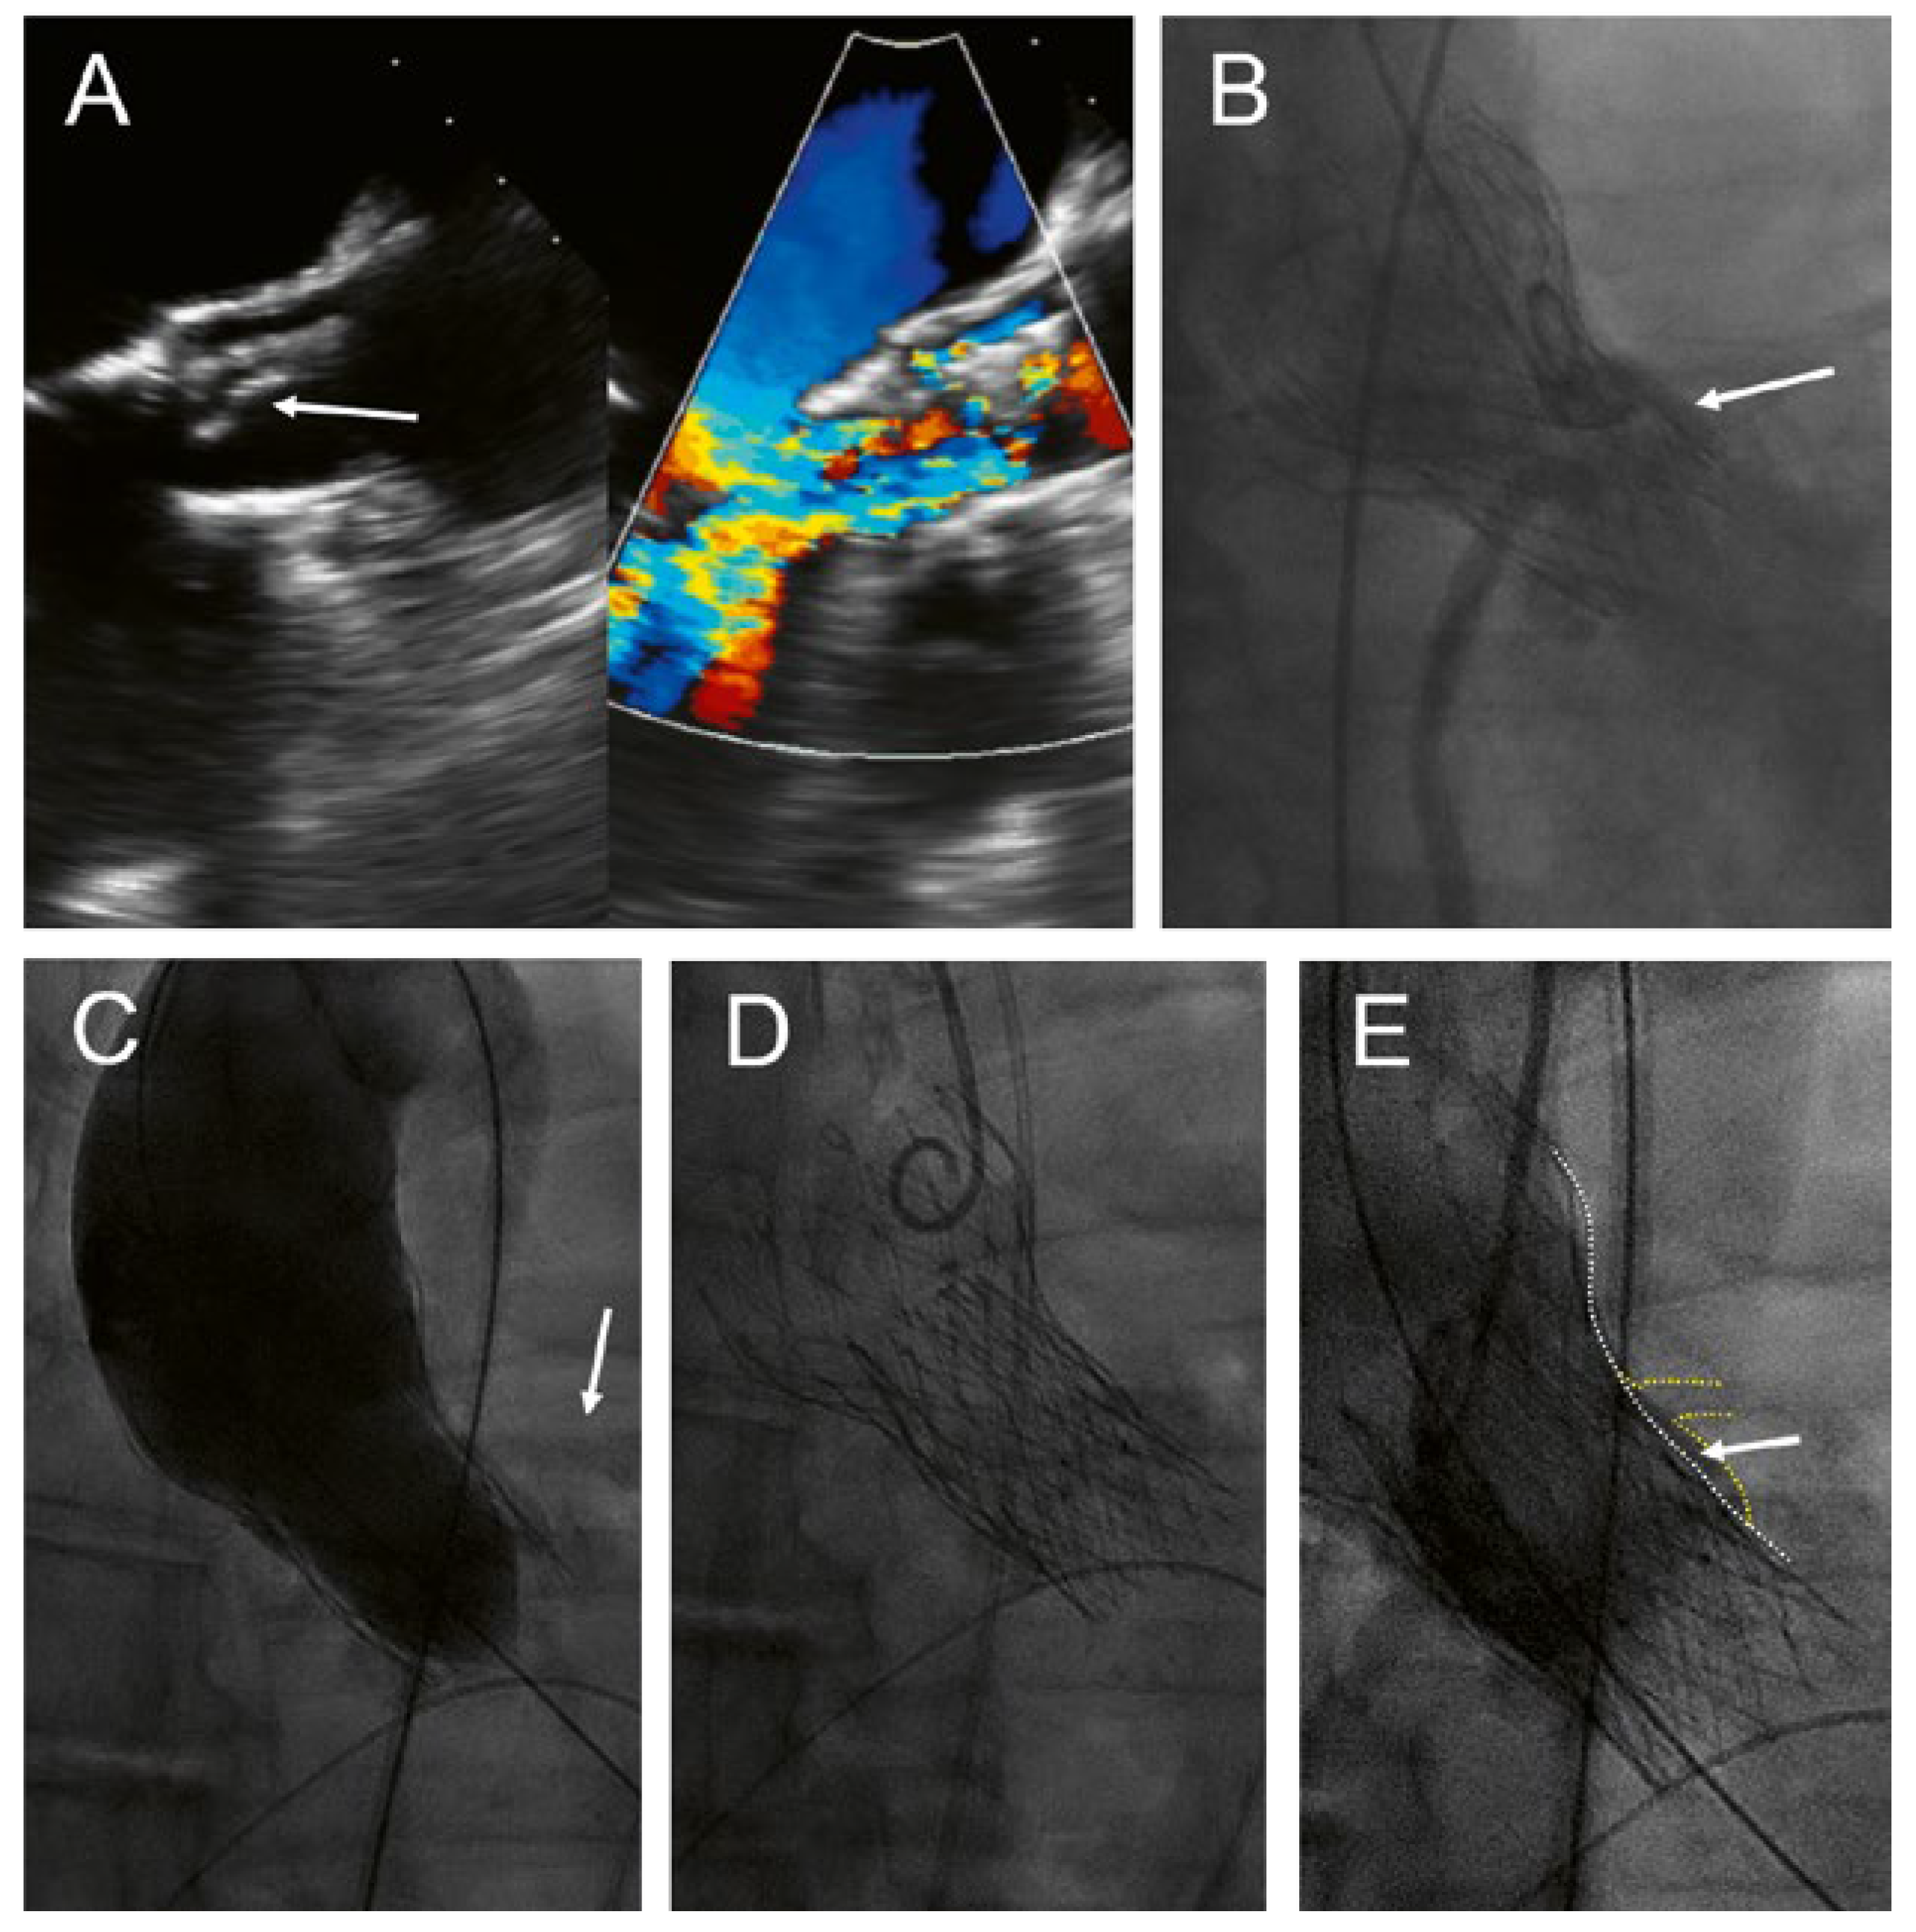

Figure 1.

Implantation of an Allegra valve in a degenerated CoreValve. This patient presented with severe transvalvular aortic regurgitation due to partial tear-off and prolapse of one of the leaflets (A, arrow). The aortic sinus was narrow with a high risk of coronary obstruction (B, arrow). An injection was performed during inflation of a 22 mm balloon to assess patency of the coronary arteries (C, arrow). Final position of the Allegra 6 mm below the inflow portion of the CoreValve (D), with only minimal space (E, arrow) between the frames of the transcatheter valves (E, white dotted line) and the sinus/left main coronary artery (E, yellow dotted line).

The patient was discussed in the interdisciplinary HeartTeam. The decision was to repeat the transcatheter aortic valve implantation with an Allegra transcatheter heart valve (THV) (NVT AG, Muri, Switzerland and NVT GmbH, Hechingen, Germany). Before implantation of the Allegra, a 22-mm TrueDilatation balloon was inflated and a supra-annular injection was performed to ensure patency of the coronary arteries (Figure 1C). Thereaher, an Allegra 27 mm was implanted about 6 mm below the inflow portion of the CoreValve (Figure 1D). Postdilatation was performed with the 22-mm TrueDilatation balloon. Postprocedural course was uneventful. Echocardiography before discharge showed a mild paravalvular leak and a mean gradient of 18 mm Hg; the calculated aortic valve area was 1.7 cm2.